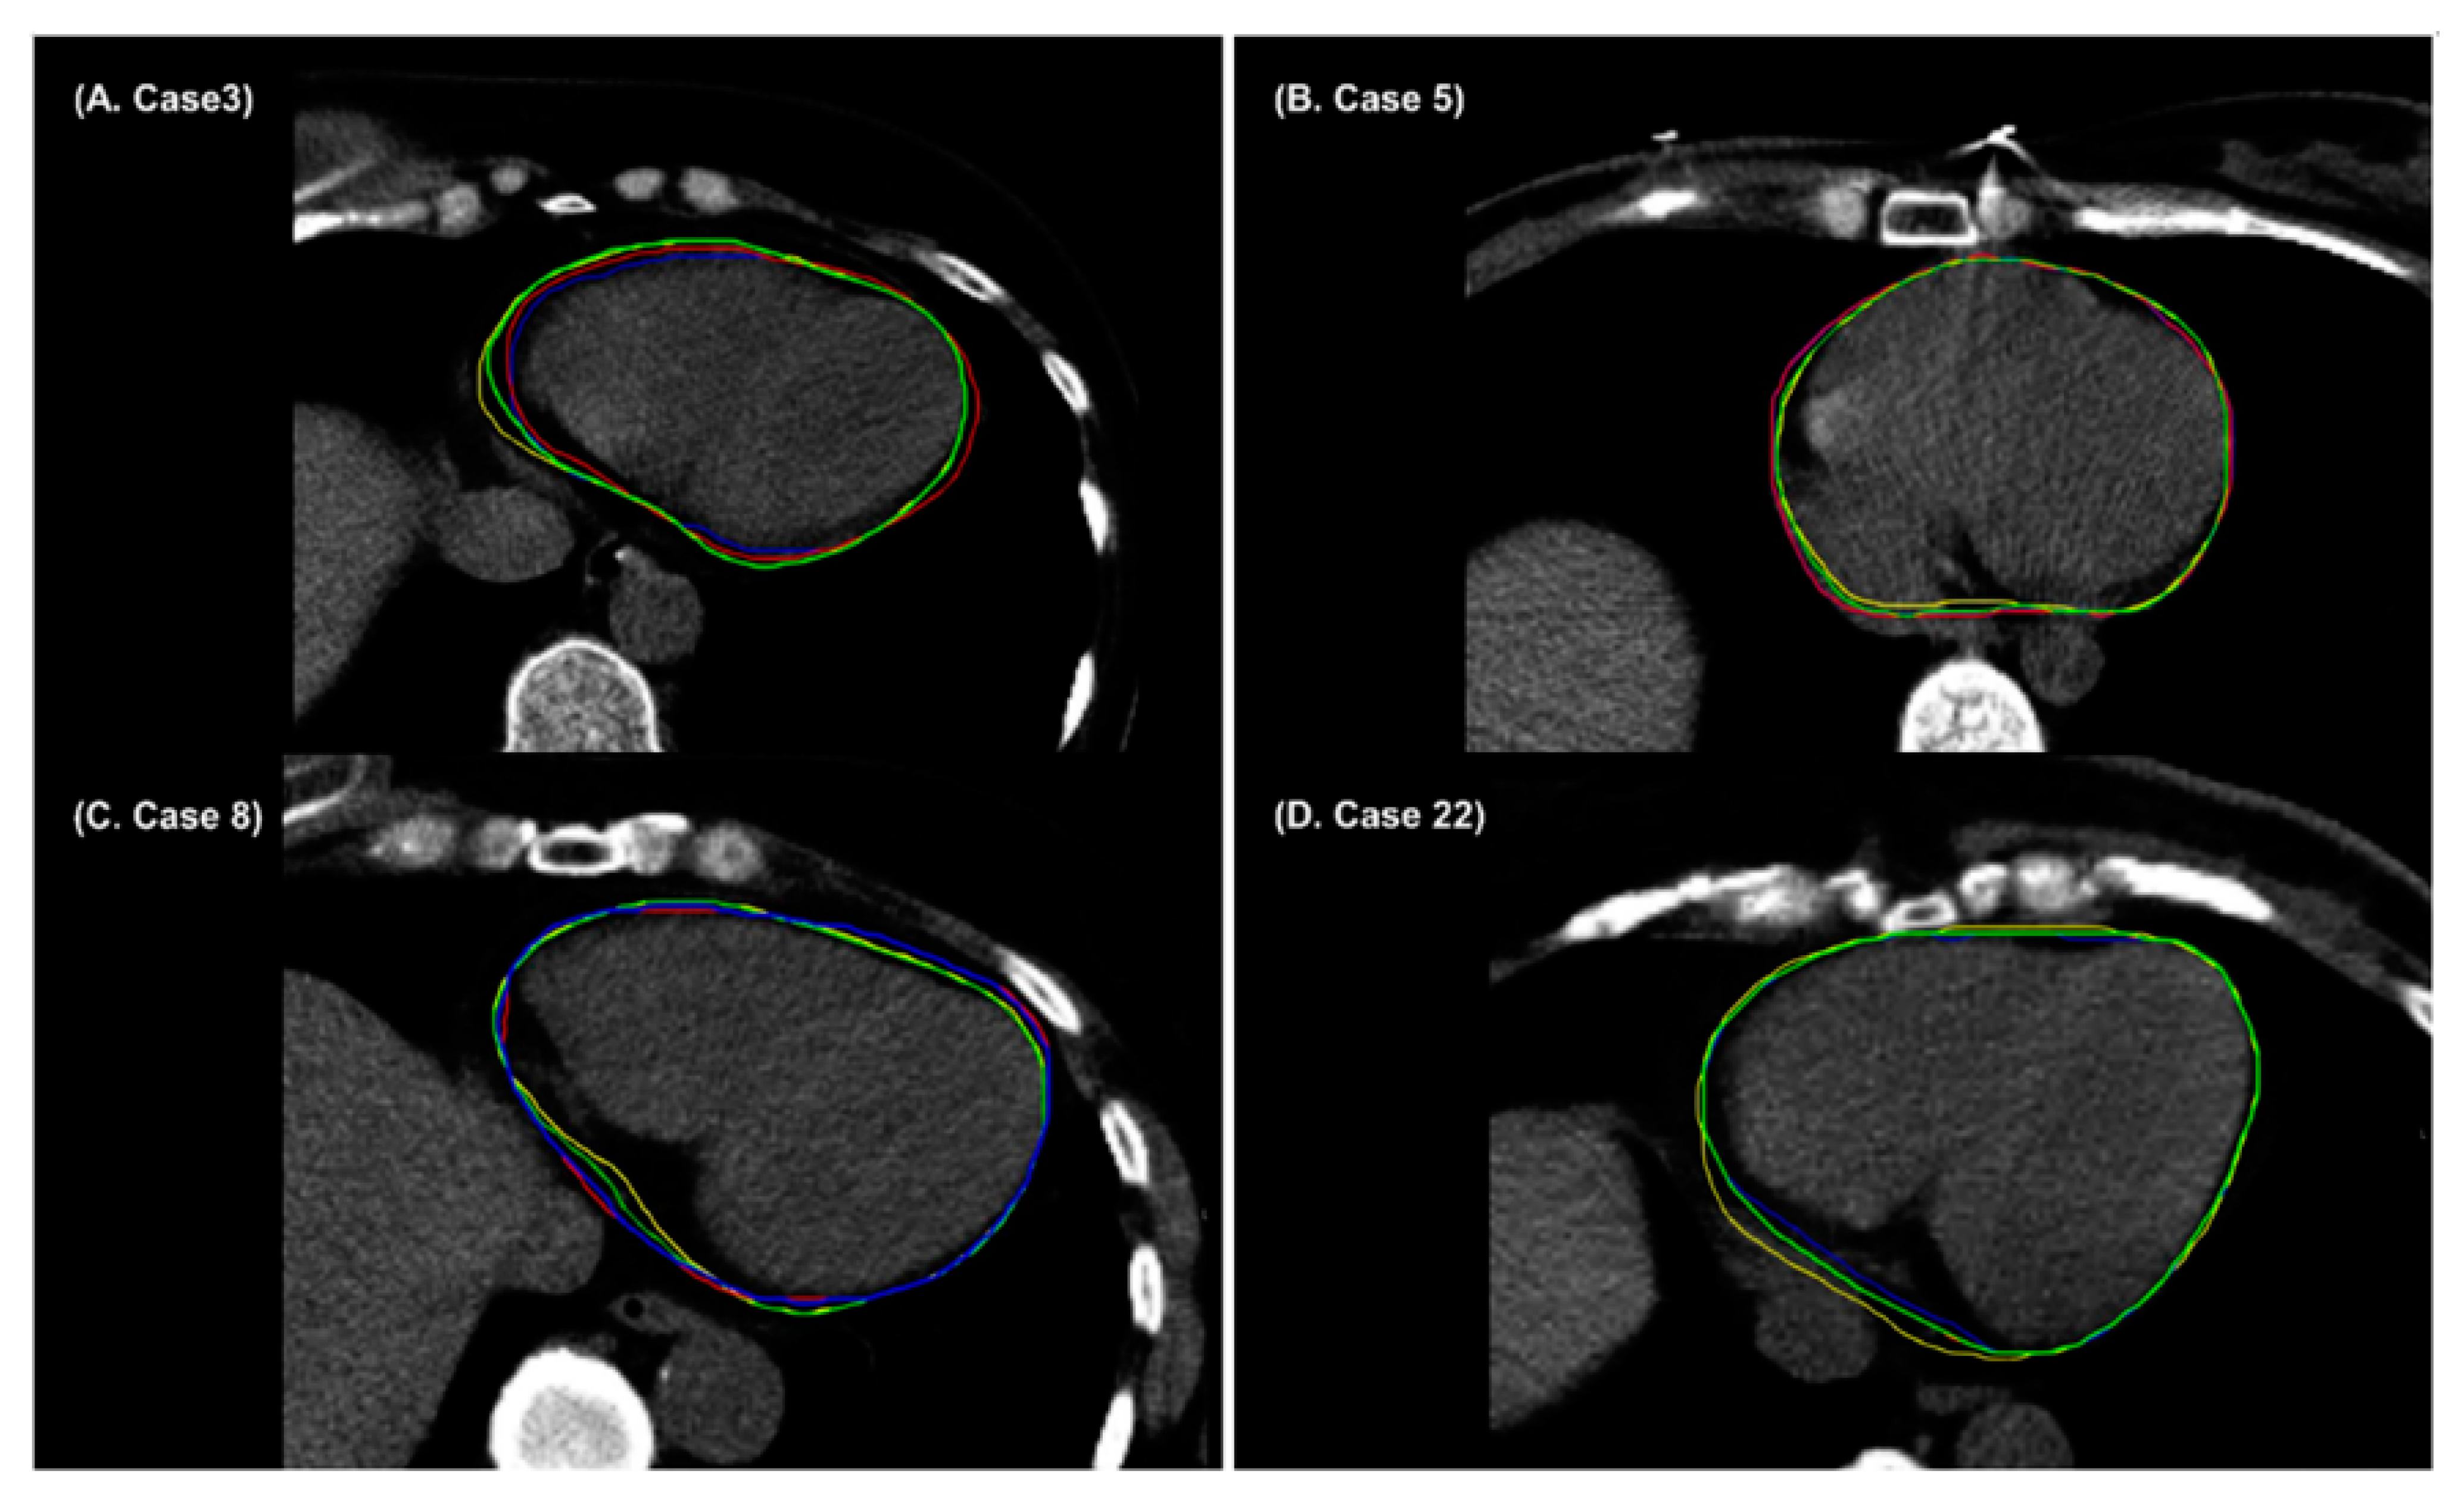

3. Results

4. Discussion